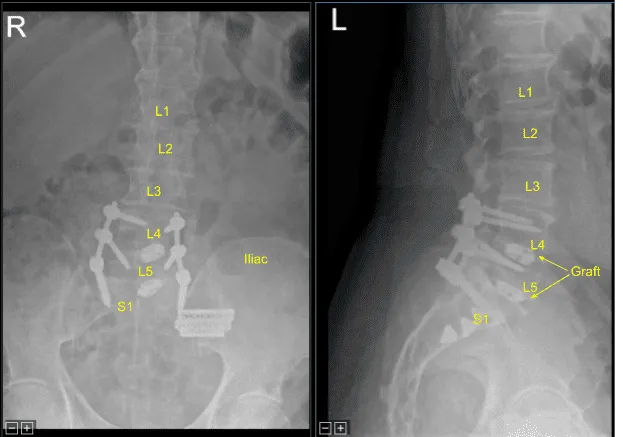

Next, morselized autograft resected from spinous processes of L4 and L5, which was morselized in the bone mill, was mixed with demineralized bone matrix allograft putty as well as bone morphogenic protein. We aspirated iliac crest bone marrow through a separate incision created for the Schanz pin with a bone marrow aspirator. This was mixed as well.

These were packed in lateral gutters and across the facet joints after decortication from L4 to S1 for arthrodesis.The wound was irrigated clear. Hemostasis was obtained with bipolar electrocautery and bone wax.